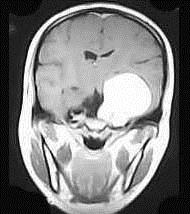

问题 女,36岁,抽搐半年,近10余天头痛加重,磁共振检查如图,选择最可能的诊断()

选项 A.胶质瘤 B.脑膜瘤 C.动静脉畸形 D.海绵状血管瘤 E.蛛网膜囊肿

答案 B